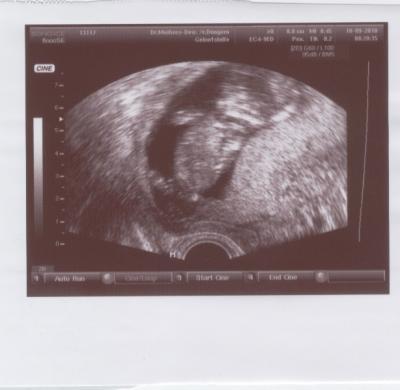

ich war heute zur VU. Alles ist bestens. Der Krümel misst mittlerweile 7 cm und war extrem in Bewegung und hat am Daumen genuckelt. Ich war so gerührt. Meine Ärztin hat sich mal wieder unheimlich viel Zeit genommen (halbe Stunde) davon waren gefühlt ein Drittel US - damit ich ein vorzeigbares Bild habe sagte sie schmunzelnd. Und weil ich so unsicher bin darf ich schon in 3 Wochen wiederkommen (01.10.). Wie schön. Vier Wochen finde ich auch immer zu lang. Tja und im Anschluß hatte ich einen Termin beim Diabetologen wg. des SS-Diabetes. Und dann kam für mich der Schock: ich muss zur Nacht Insulin spritzen. Und das obwohl ich mich so strikt an die Ernährungsvorgaben gehalten habe. Das saß - ich bin erst mal in Tränen ausgebrochen. Aber ich habe mich mittlerweile wieder eingekriegt. Der positive Nebeneffekt - anstatt zu nehme ich nur noch ab. Aber Hauptsache dem Krümel geht es gut. Alles andere lässt sich in den Griff kriegen.